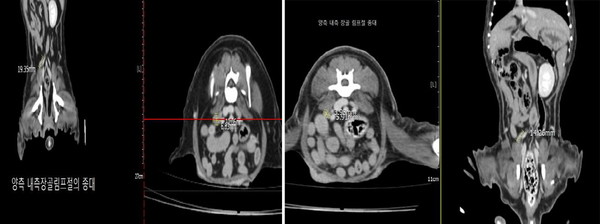

이번 실험에서는 반려견에게 폴리탁셀의 약물 부작용이 나타나지 않는 최대무독성용량(NOAEL) 이하인 4.5㎎/㎏을 회복기 없이 주 1회씩 3회 연속 투여하고 3주 후에 관찰한 결과, 유선종양 크기가 투약 전보다 무려 76.78% 감소했다. 특히 림프절에 전이된 종양 크기는 투약 전보다 74.01%나 줄어들어 폴리탁셀이 전이암 치료효과도 뛰어남을 입증했다.

이번 실험에 참여한 반려견의 종양은 사람처럼 자연적으로 발생한 것으로, 반려견 실험 결과는 사람을 대상으로 한 임상 전망을 더욱 밝게 해준다. 현대바이오 부사장 진근우 박사는 "5년 전 폴리탁셀은 췌장암 이식 쥐 모델에서 뛰어난 안전성과 효능을 입증한 바 있다"며 "폴리탁셀이 이번에 사람과 쥐보다 항암제의 독성과 부작용에 훨씬 민감한 반려견의 자연발생 유선암에 안전성과 효능을 입증함으로써 사람을 대상으로 한 임상의 성공 가능성도 그만큼 커졌다"고 말했다.